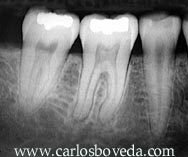

Endodoncia Interactiva 15 a - Carlos Bóveda Z. - Venezuela

RODE - Revista de Operatoria Dental y Endodoncia - ENDODONCIA:Reendodoncia diente 4.6